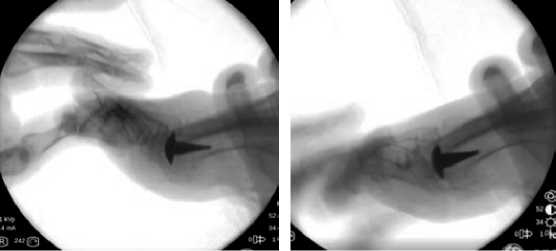

В Центре Хирургии стопы ГКБ им. С. С. Юдина по описанной методике с минимальным периодом наблюдения более 12 месяцев прооперирован 21 пациент. Женщин было 17 (81,0 %), мужчин 4 (19,0 %). Средний возраст пациентов составил 61 лет ± 7,7 (43–72). Пациентов старше 60 лет – 57,4 % (12 пациентов). Среди данной группы пациентов нами не было выявлено инфекционных осложнений и признаков нестабильности гемиэндопротеза. Средняя амплитуда движений 1 ПФС без нагрузки: до лечения — 15° ± 3,3 (5°–20°), на момент контрольного осмотра через 12 месяцев 25° ± 3,8 (15°–30°). Средняя амплитуда движений 1 ПФС с физиологической нагрузкой с имитацией фазы предпереноса: до лечения— 15° ± 3,0 (10°–25°), через 12 месяцев после лечения— 35° ± 5,2 (25°–45°) (рис. 8). Результаты анкетирования пациентов с помощью визуальной аналоговой шкалы (ВАШ) до операции составили 7,7 ± 1,9 (4–10) баллов. Через 12 месяцев после проведенного лечения результаты анкетирования ВАШ составили 1,6 ± 0,8 (0-3) баллов. Анкетирование шкалой American Orthopaedic Foot and Ankle Society Hallux Score (AOFAS HS) также позволяет сделать вывод о наличии положительной динамики до и через 12 месяцев после проведенного лечения: до операции – 35,5 ± 10,9 (18-52), через 12 месяцев – 82,7 ± 5,2 (73–90). Показатели шкалы Foot Function Index (FFI) на момент предоперационного осмотра равнялись 63,5% ± 9,9 (48%–82%), через 12 месяцев – 10,5% ± 2,5 (7%–16%).

Рис. 7. Оценка амплитуды движений с нагрузкой с имитацией фазы предпереноса

Fig. 7. Evaluation of the amplitude of movements with a load with the imitation of the pre-swing phase